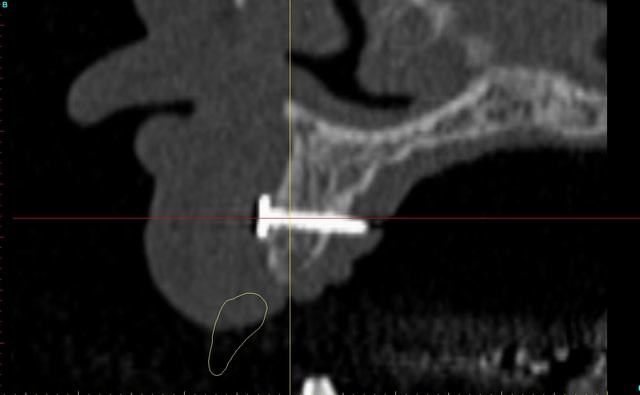

dentiste57 écrivait:

--------------------

> et là ?

> greffe selon ta méthode ?

Cross section dhvkc8 - Eugenol

3d dt3qom - Eugenol

Overview uqcp6u - Eugenol

S2y2o1v7q53ws4r5wy6ou8czrpom - Eugenol

pxav

01/05/2011 à 12h55

> dentiste57 écrivait:

> --------------------

> > et là ?

> > greffe selon ta méthode ?

expansion, c'est plus cool!